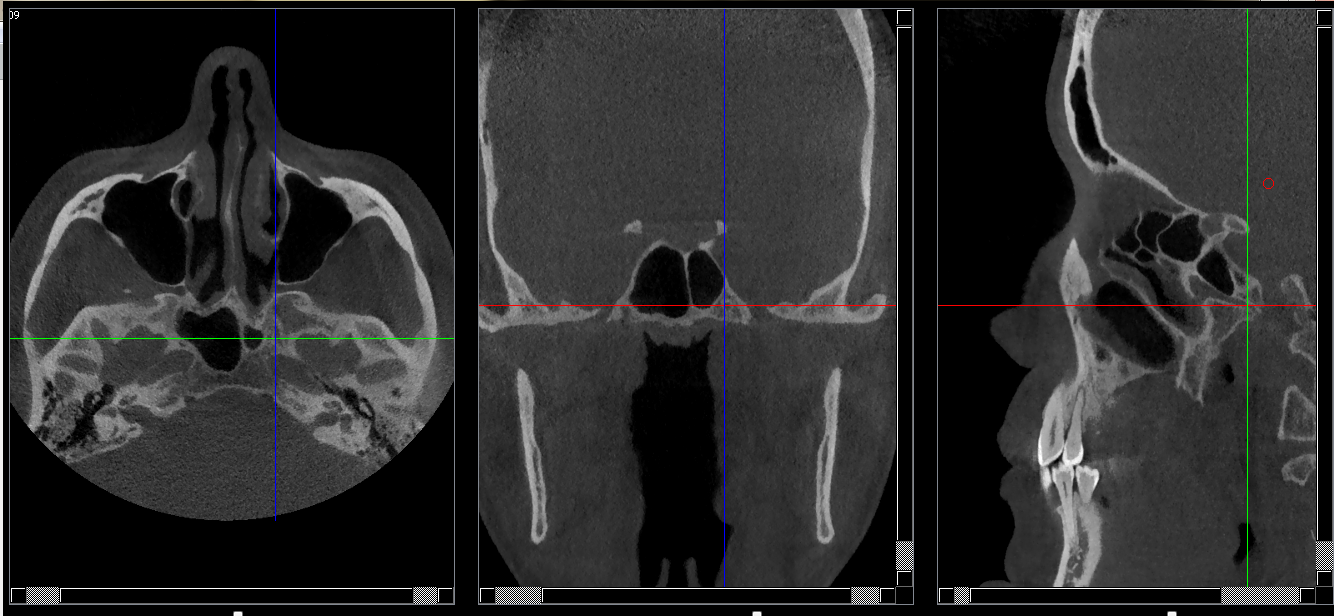

Structures osseuses

Foramen rotundum

Repères anatomiques

- Coupe transversale

- Début : Grande aile du sphénoide

- Fin : Sinus sphénoide

- Coupe frontale

- Début : Sinus sphénoide

- Fin : Clivus

- Coupe saggitale

- Début : Côté droit du processus clinoide

- Fin : Côté gauche du processus clinoide